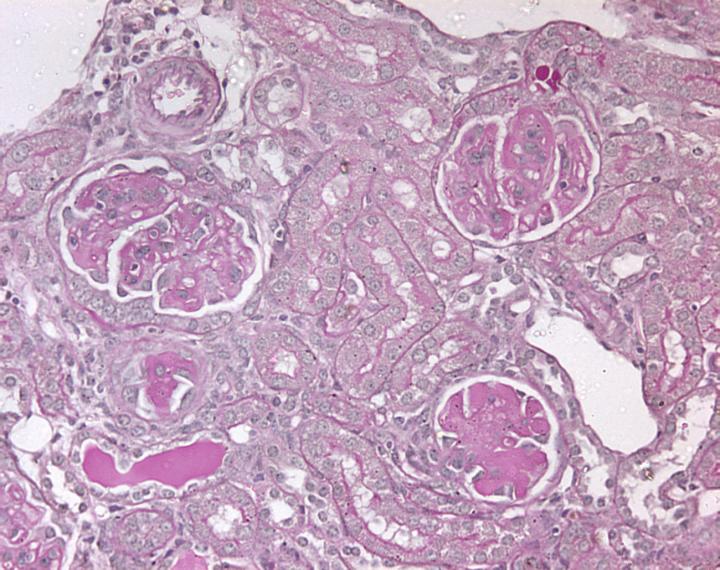

Many different diseases and insults can injure kidneys, resulting in kidney failure. Some autoimmune diseases damage glomeruli (the 'filtering units' of the kidney), while problems with the tubules (for example, impaired blood flow to the kidney at the time of renal transplantation, radio-contrast dye or drugs) can cause acute kidney injury (AKI). A common outcome in either type of injury is that immune cells infiltrate the kidney and this inflammation can result in permanent scarring.

We have reviewed the research that indicates that IL-17A/F and Th17 cells contribute to renal injury. Animal studies of diseases damaging glomeruli suggest that they are involved in the initial inflammatory response within the kidney. In studies of patients with autoimmune diseases, such as systemic lupus erythematosus, elevated IL-17A levels and higher proportions of Th17 cells in circulating blood have been found, correlating with disease severity. Animal models of AKI have demonstrated that administration of an antibody against IL-17A reduces renal injury. Therefore, blockade of IL-17A/F signaling may be a promising avenue to explore in clinical trials as a novel therapy for the treatment and prevention of immune mediated renal diseases.